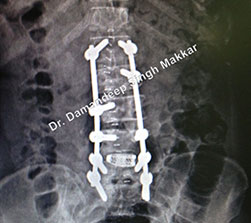

orthopedic spine surgeon Dr Damandeep Singh Makkar in India

orthopedic spine surgeon case study treatment in Punjab hospital

lumbar spine fusion surgery performed by Dr Makkar in Ludhiana